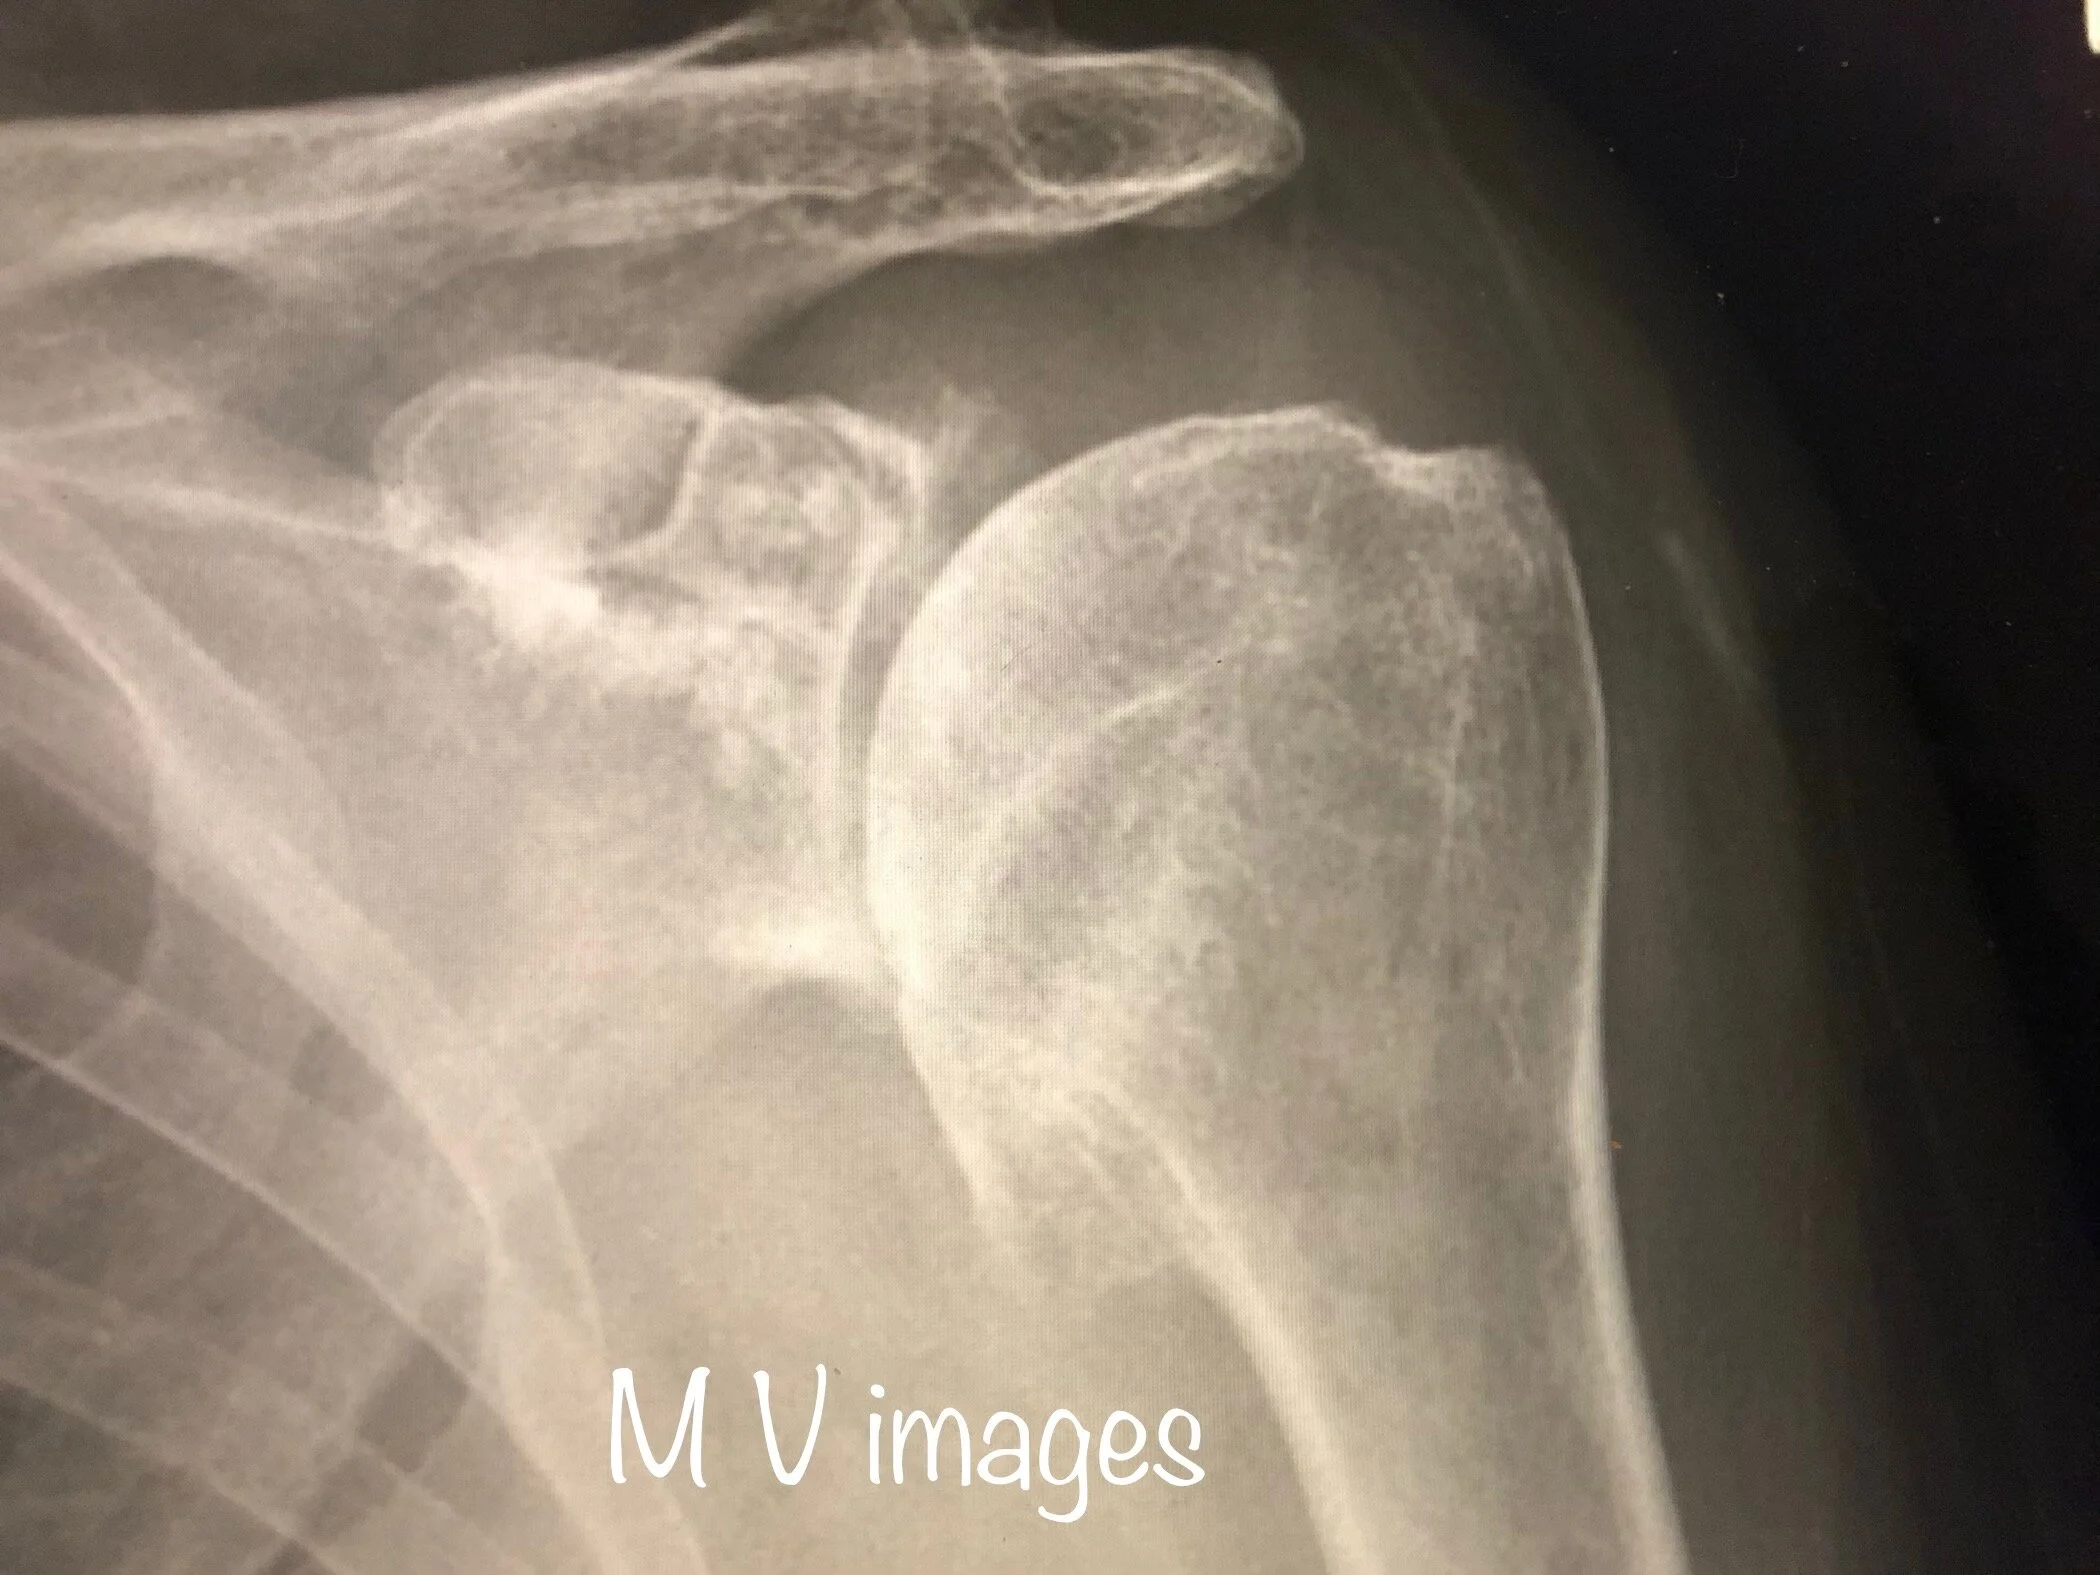

Before joint replacement

Advanced shoulder arthritis can result in the total loss of the smooth cartilage resulting in painful and stiff movement.

The above image is a X-ray of a shoulder with advanced shoulder arthritis with osteophytes. The patient had severe shoulder pain with poor quality of life and required joint replacement.